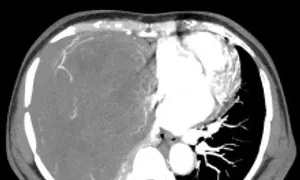

Hình ảnh khối u choán hết khoang lồng ngực của bệnh nhân. Ảnh: Bệnh viện cung cấp

Bệnh nhân cho biết lý do không phẫu thuật khi ấy bởi u nhỏ không gây khó chịu. Gần đây bà khó thở, sức khỏe giảm sút, sụt 5 kg. Bác sĩ Bệnh viện Ung bướu Hà Nội khám ghi nhận lồng ngực phải bệnh nhân có khối đặc kích thước 20x15 cm đè xẹp phổi, thâm nhiễm trung thất, thành ngực. Sinh thiết khối u kết quả giải phẫu bệnh là u xơ đơn độc.

Bác sĩ tiên lượng ca mổ lấy u nhiều khó khăn do bệnh nhân có thể trạng gầy yếu, khối u lớn giàu mạch nuôi chiếm gần hết khoang lồng ngực. Ngày 30/9, TS.BS. Phan Lê Thắng, Trưởng khoa Ngoại Theo yêu cầu, Bệnh viện Ung Bướu Hà Nội, cho biết êkíp phẫu thuật hội chẩn tính toán kỹ phương án mổ, khống chế nguồn mạch máu nuôi để hạn chế mất máu cho bệnh nhân. Khối u được bóc tách thành công, nặng hơn 2 kg.